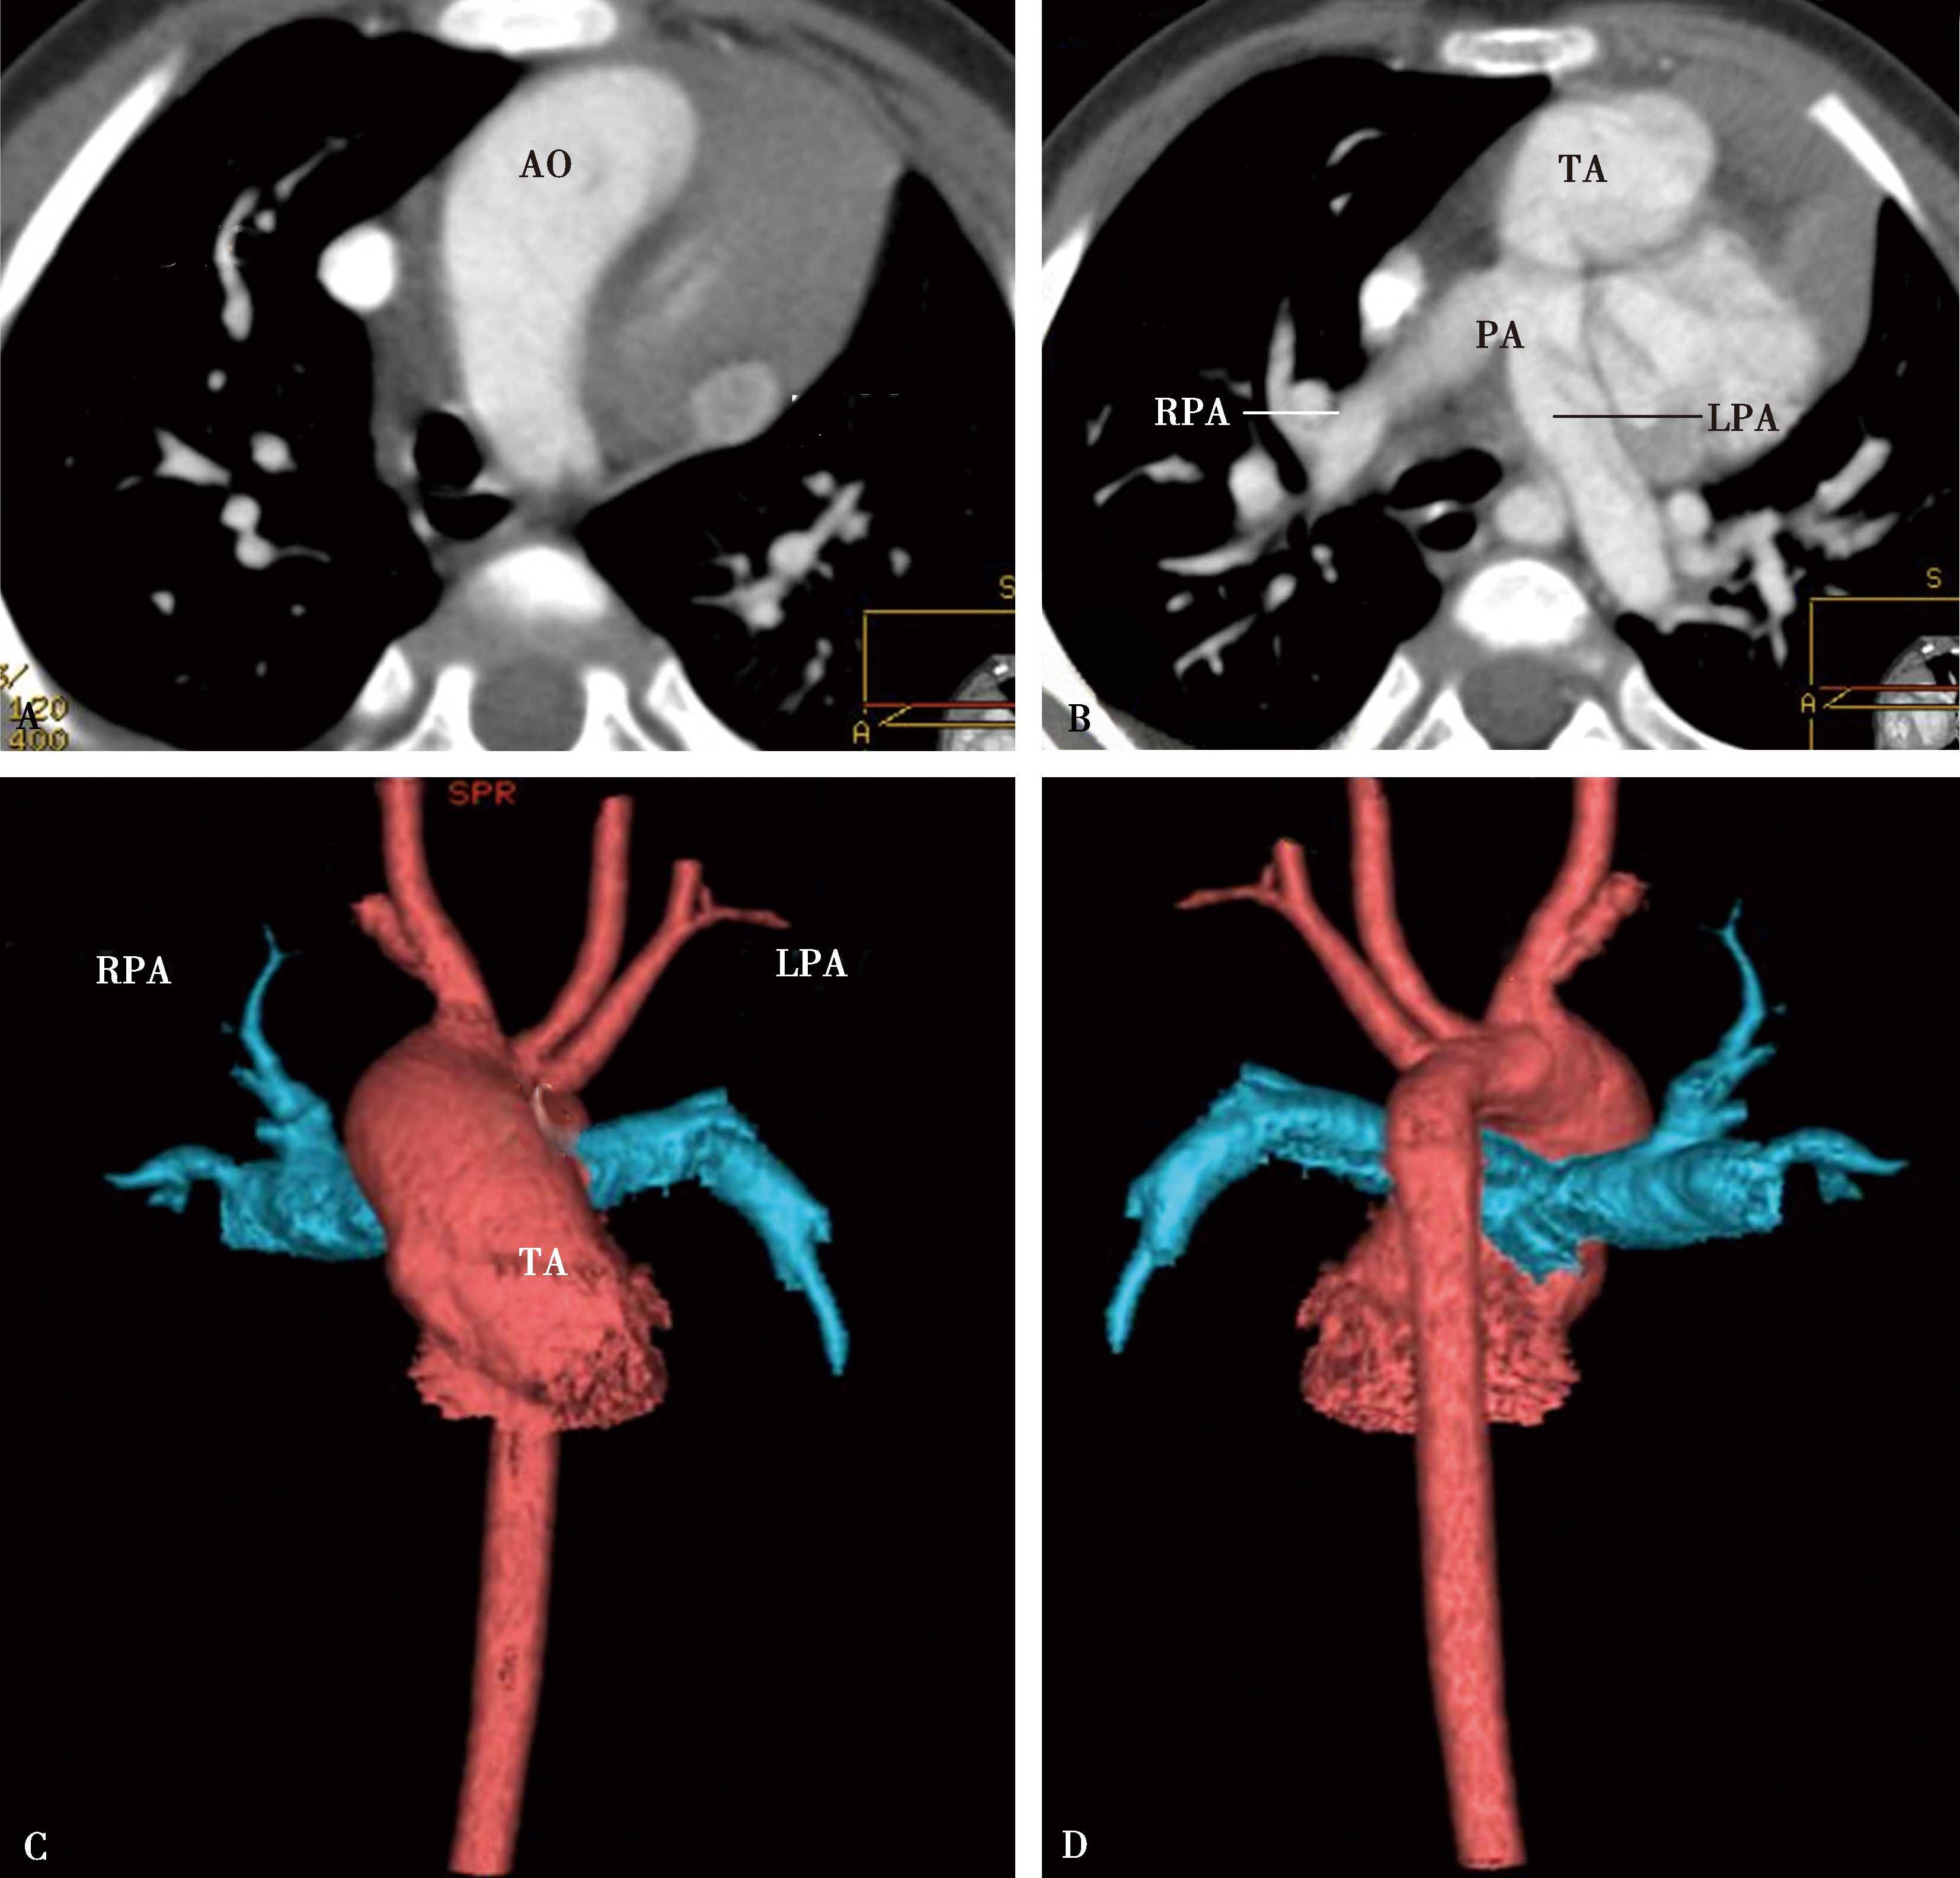

肺动脉受累表现为主肺动脉及左右肺动脉外形不规则,粗细不均,不同程度狭窄-闭塞、与瘤样扩张交替出现;管壁钙化;可以出现肺动脉高压征象,右心房室扩大(图8-6-1,图8-6-2)。

A、B.横断图像,右肺动脉被纵隔纤维化包围重度狭窄-闭塞(A↑);右侧肺血少(B↑),左侧肺血多(B↑);肺动脉高压,右心房扩大。AO:升主动脉;PA:肺动脉;RPA:右肺动脉;LPA:左肺动脉

图8-6-2 男,34岁,慢性纵隔炎(结核性)肺动脉、主动脉受累,肺动脉高压

A、B.横断扫描纵隔增宽,纵隔胸膜增厚,主动脉与肺动脉间低密度脂肪间隙消失,代之以中等密度(结缔组织),主动脉、主肺动脉及左右肺动脉外形不规则,粗细不均,钙化。主肺动脉及右肺动脉狭窄为主,左肺动脉瘤样扩张;C、D.肺动脉三维重建,示主肺动脉及右肺动脉粗细不均,不规则狭窄,主肺动脉瘤扩张。PA:主肺动脉;LPA:主肺动脉;RPA:右肺动脉;AO:升主动脉